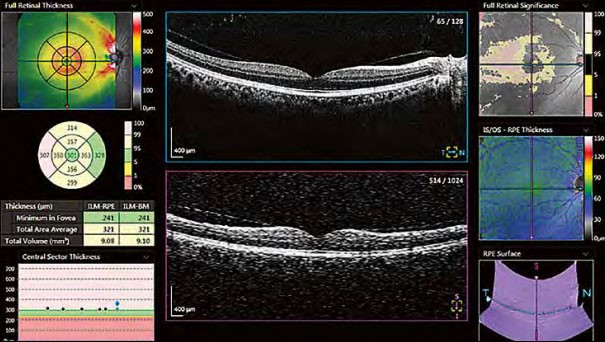

Макула

Система забезпечує детальний аналіз товщини сітківки за допомогою порівнянь з нормативними базами даних, сітками ETDRS, різними таблицями та 3D-візуалізаціями.

Глаукома

Раннє виявлення глаукоми є запорукою уповільнення її прогресування. Xephilio OCT-A1 підтримує вимірювання NFL + GCL + IPL та GCL + IPL з широким набором графічних зображень для повного аналізу.

Оптичний диск

Xephilio OCT-A1 дозволяє всебічно проаналізувати всі параметри оптичного диска, та порівняти їх за допомогою широкої нормативної бази даних.

Звіт про прогрес

Результатом аналізу є порівняння п’яти обстежень, що зроблені у різні проміжки часу на тому ж самому оку в однакових режимі сканування та розміру області сканування.